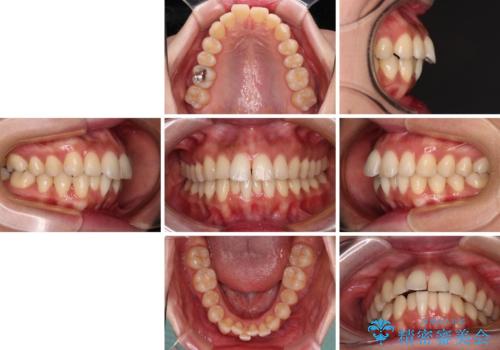

- 口元の閉じにくさを気にして来院された患者様です。

上下ともに歯列が前方に突出していたため、上下左右の第一小臼歯4本を抜去し、ワイヤー装置による矯正治療を行うこととしました。

舌の突出癖による影響もあったため、舌のトレーニングを並行して実施しました。

舌の突出癖がなかなか改善されず、上下前歯の接触がやや甘い状態での仕上がりとなりました。

接触が甘い場合、上顎前歯の叢生が後戻りを起こしやすくなるため、治療終了後の保定期間でも舌のトレーニングを継続するように指示しています。